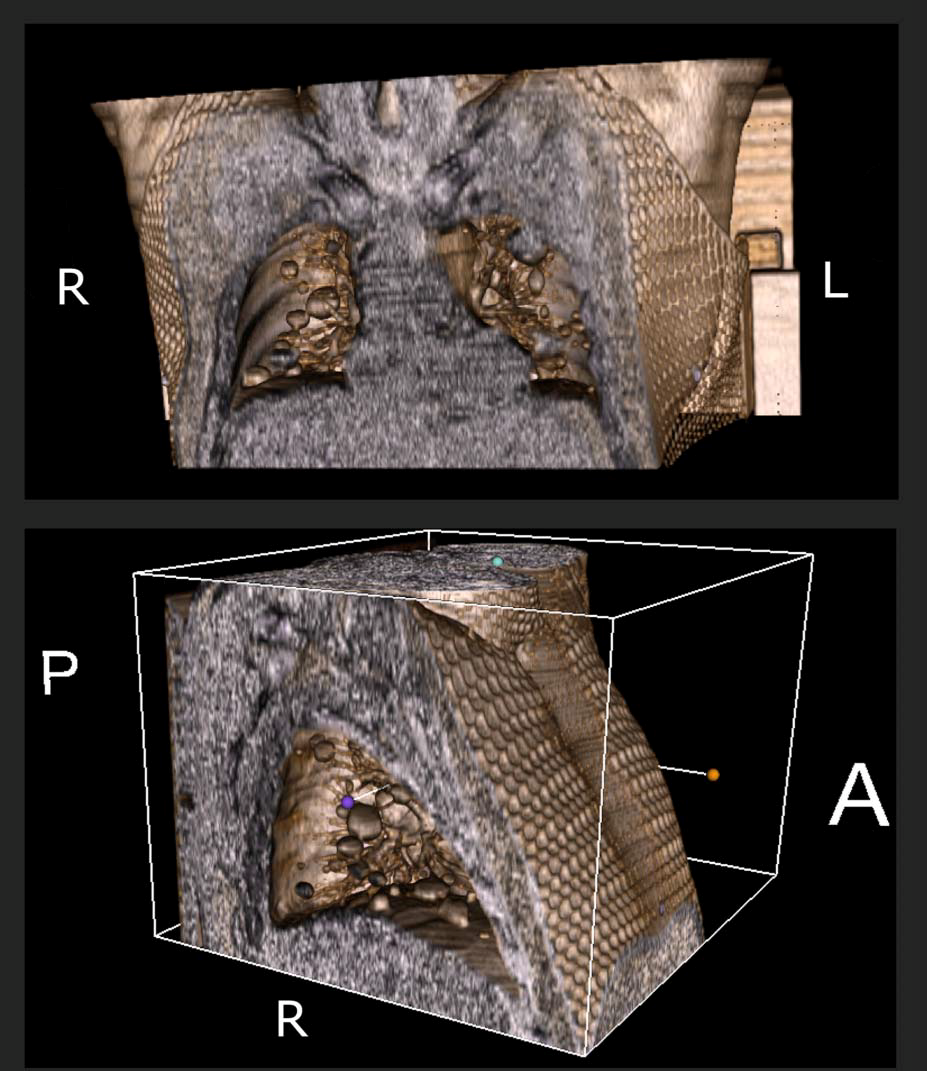

两上肺巨大对称转移瘤?

图片尺寸4000x3000